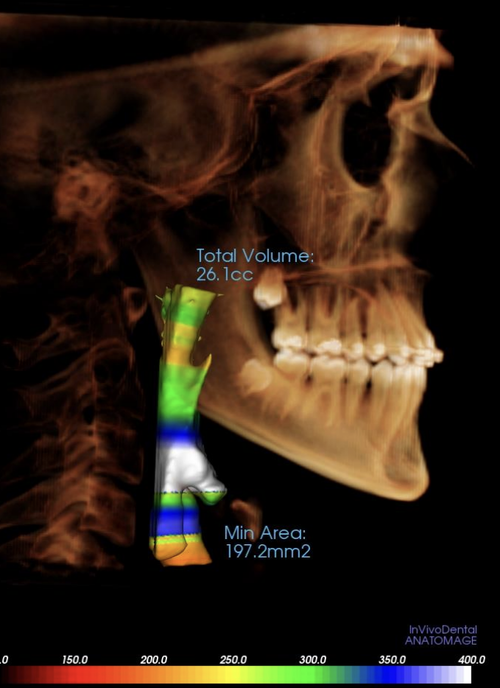

I slouched my way through my early teens and got fed fucking slop when i was a child. My maxilla is recessed and i convinced my parents to get a skull scan done for me, in hopes of getting MSE. I know that my ccw is cooked and i need to work on hella things. The doctor that did the scan said she can put in aligners to widen my upper palatte, idk if its cope or not, the main problem is that my ortho keeps ignoring my problem and just says my upper jaw looks fine. Ice made an appointment with a CMD and will go there in a few days, does anyone have any tips on what to tell them to possibly get MSE? You can see that my maxilla is recessed on the scan, Ive attached it below

TELL ME WHAT YOU THINK

I slouched my way through my early teens and got fed fucking slop when i was a child. My maxilla is recessed and i convinced my parents to get a skull scan done for me, in hopes of getting MSE. I know that my ccw is cooked and i need to work on hella things. The doctor that did the scan said she can put in aligners to widen my upper palatte, idk if its cope or not, the main problem is that my ortho keeps ignoring my problem and just says my upper jaw looks fine. Ice made an appointment with a CMD and will go there in a few days, does anyone have any tips on what to tell them to possibly get MSE? You can see that my maxilla is recessed on the scan, Ive attached it below

TELL ME WHAT YOU THINK